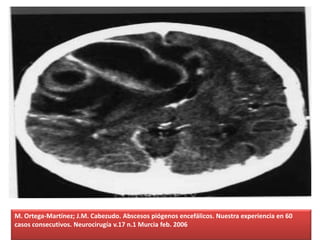

Los corticoides, que hemos utilizado en un 75% de los

pacientes, son un tratamiento controvertido. Se sabe que los

esteroides restablecen la integridad de la barrera

hematoencefálica, disminuyendo su permeabilidad, dando

lugar a una rápida desaparición del edema

cerebral, mejorando los déficits del paciente y su nivel de

conciencia.

Pero su propia actividad antiinflamatoria e inmunosupresora es la

que los convierte en un tratamiento discutido en el caso de las

infecciones cerebrales.

M. Ortega-Martínez; J.M. Cabezudo. Abscesos piógenos encefálicos. Nuestra experiencia en 60

casos consecutivos. Neurocirugía v.17 n.1 Murcia feb. 2006

Según pusieron de relieve Quartey y cols. en 1976, los corticoides

dificultan el encapsulamiento de la infección y facilitan su

diseminación.

Esta conclusión, no obstante, no fue ratificada plenamente por

Schroeder y cols. en un trabajo posterior (1987), quienes apreciaron

sólo un retraso en la encapsulación, sin afectar a la mortalidad.

Pese a ello, se aconseja restringir el uso de los esteroides a los casos

de pacientes con incremento de la PIC con riesgo de enclavamiento y

retirarlos tan pronto como sea posible.

Entre nosotros se han utilizado en un 75% de los pacientes, sin que

parezcan haber influido de manera decisiva en el resultado final.